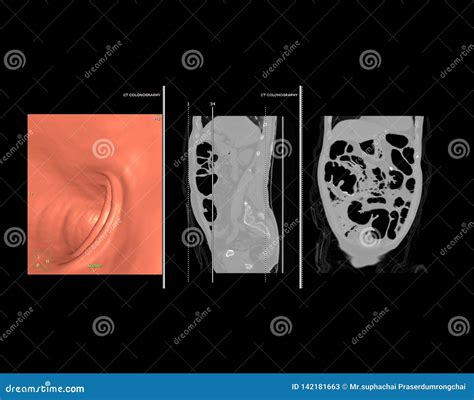

Preventative health screenings are a cornerstone of modern medicine, particularly when it comes to early detection of colorectal issues. Among the various diagnostic tools available, Ct Scan Colonography—often referred to as virtual colonoscopy—has emerged as a highly effective, minimally invasive alternative to traditional invasive procedures. By utilizing advanced imaging technology, medical professionals can visualize the interior of the colon and rectum with remarkable clarity, allowing for the identification of polyps or other abnormalities without the need for sedation or the insertion of a long, flexible tube.

At its core, Ct Scan Colonography is a specialized radiological imaging test that produces 2D and 3D images of the large intestine. Unlike a standard colonoscopy, which involves physical exploration of the bowel, this procedure relies on computed tomography (CT) to create a detailed internal map. The process requires the patient’s colon to be inflated with air or carbon dioxide to ensure the walls of the bowel are fully distended, which allows the CT scanner to capture clear, unobstructed views of the lining.

This diagnostic method is particularly favored by patients who may be anxious about the sedation required for standard colonoscopies or those who have specific anatomical contraindications that make traditional procedures more difficult. Because it is quick and generally well-tolerated, it serves as an excellent screening tool for those at average risk of colorectal cancer.